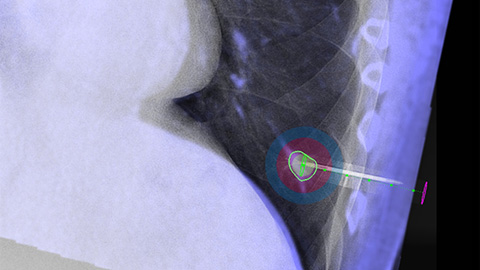

XperGuide Ablation provides comprehensive assistance for treatment planning and live needle guidance. It offers unique Parallax Correction to plan needle trajectories for off-center lesions [9].

XperGuide Ablation displays the virtual needle path to assist in multiple needle planning. It shows needle characteristics such as ablation zone/isotherm to confirm complete tumor coverage prior to ablation.

Clarity IQ produces finely tuned high-definition fluoroscopic images with superb detail to assist with needle progression to target [6].

XperGuide provides highly accurate live image guidance of each needle to a targeted position by overlaying pre-planned trajectories with fluoroscopic imaging [10].

With CBCT acquire a post-ablation CBCT to demonstrate the extent of tumor coverage and confirm completeness of your treatment.